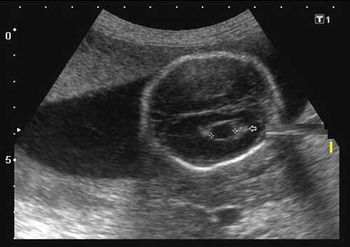

Do these images of the fetal brain point to a congenital anomaly or something else?

This second-trimester fetus has a renal abnormality. Can you identify it?